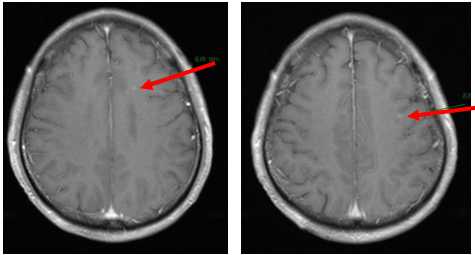

辅助检查

PET-CT(2023年9月):右下肺叶发现6.9×6.7×6.6cm的FDG高摄取肿块,伴右侧第7、8肋骨侵犯可疑,右肺门淋巴结肿大,双肺上叶多发结节,考虑腺癌谱系疾病。

CT及PET-CT随访(2023年11月、2024年1月):评估新辅助治疗效果,右下肺叶肿块缩小,右肺门淋巴结代谢活性消失,右肺上叶结节稳定但代谢活性降低,左肺上叶及双侧磨玻璃样病变稳定。

新辅助治疗:患者接受4周期新辅助化疗联合免疫治疗(培美曲塞、顺铂、纳武利尤单抗),治疗后影像学显示肿块缩小,代谢活性降低。